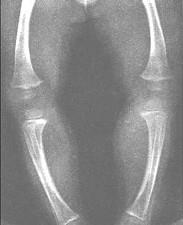

问题 佝偻病活动极期长骨X线检查可显示 ( )

选项 A.可有骨质缺损 B.可有骨干弯曲或骨折 C.骨质普遍稀疏,密度降低 D.干骺端增宽,钙化预备带消失,呈毛刷状改变 E.骨骺与干骺端距离加大

答案 BCDE